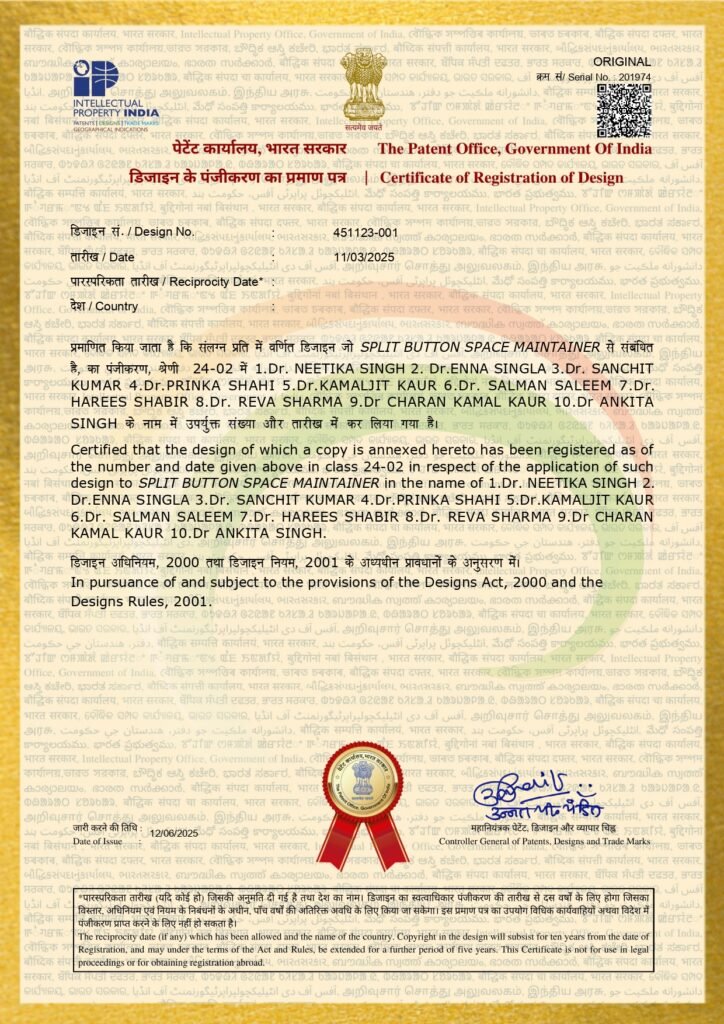

- Space Maintainers

- Dr. Kamaljit Kaur